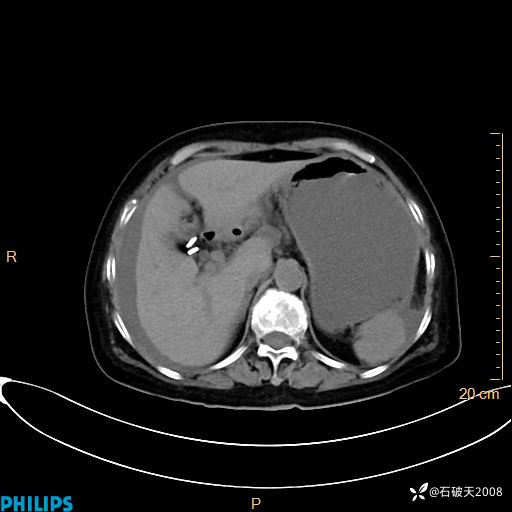

MIP